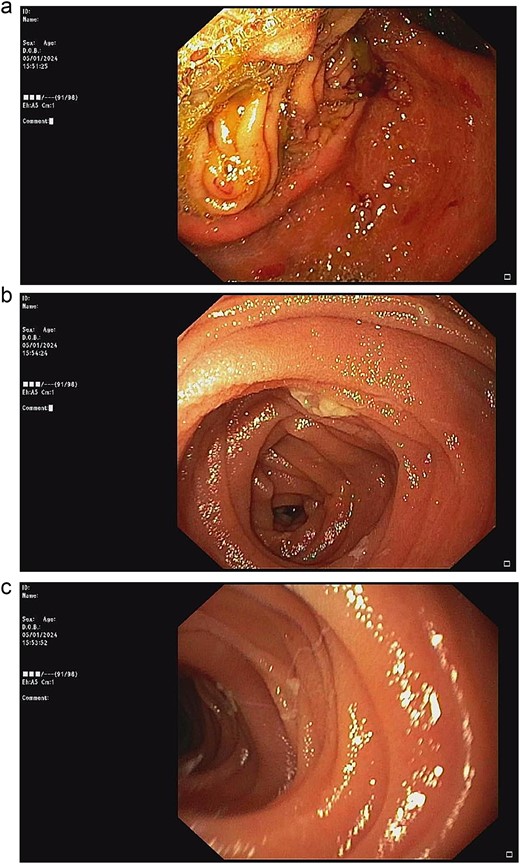

Double naso-enteric tubes was placed for stenting, enteric feeding and decompression (one was in the distal efferent limb, the other was in the proximal afferent limb). Savary-Gilliard guidewires were placed through-the-scope, across the angulated point. The endoscope was then totally withdrawn, leaving the guidewire in place. Naso-enteric tubes were threaded over the guidewire across the obstructed segment by using two 16-French single lumen plastic nasogastric tube (125 cm in length). The position of the tubes was confirmed by fluoroscopy and contrast study (Fig. 3).

Fluoroscopy and contrast study: (a) Savary-Gilliard guidewires were placed, (b) naso-enteric tubes were placed (*: afferent limb, #: efferent limb).